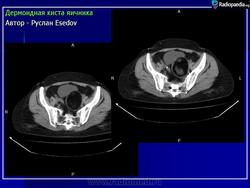

Дермоидная киста.